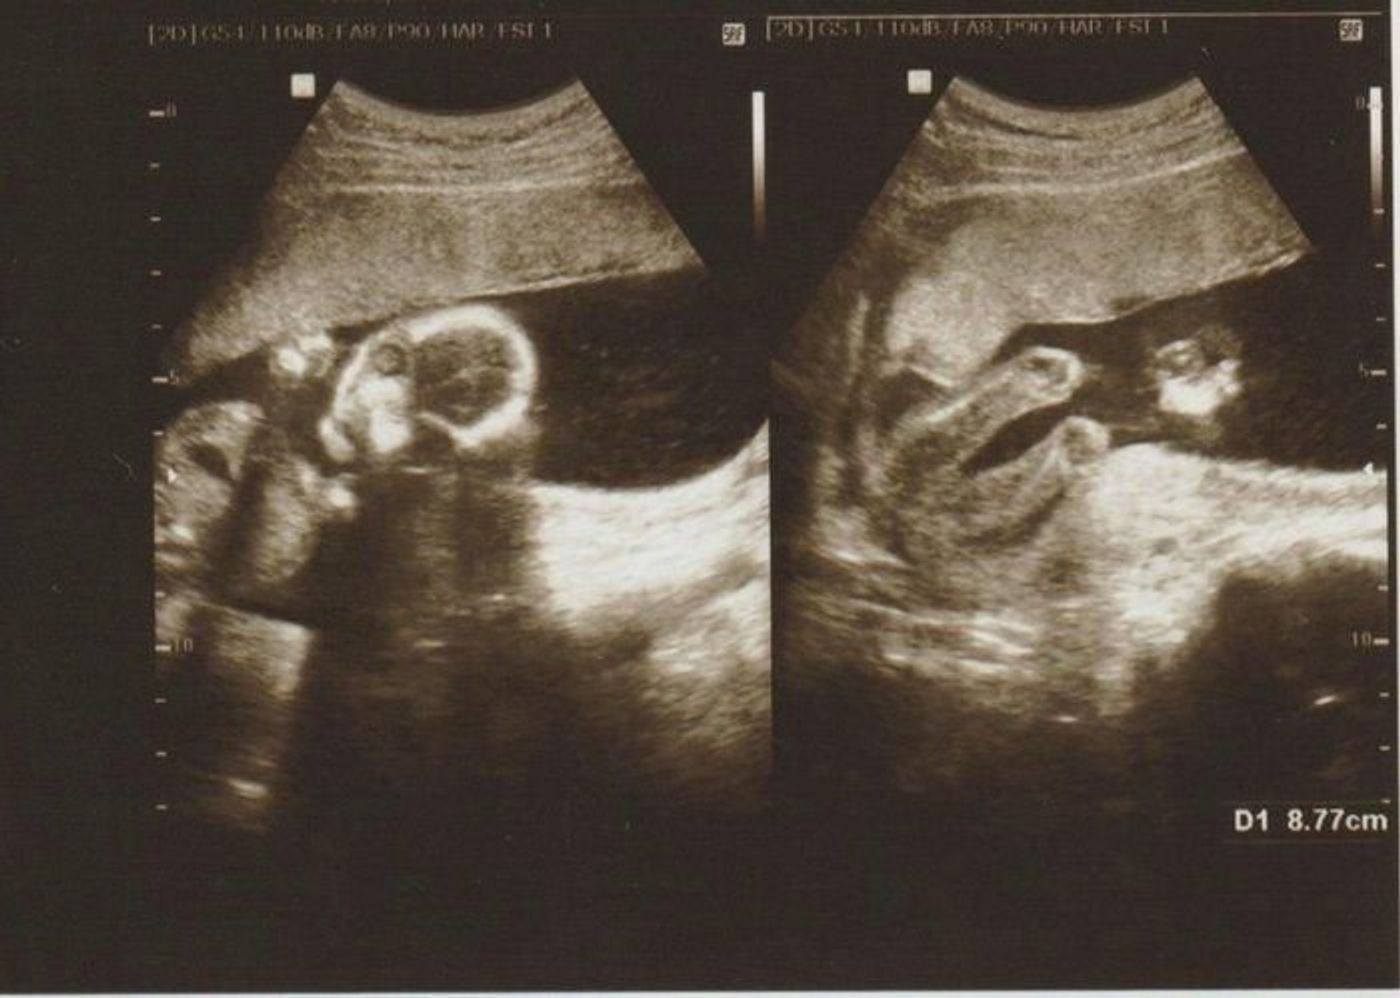

女の子はなかなか性別確定に至らない 妊娠16週、つまり妊娠5ヶ月には、比較的胎児と母体の状態が安定した、安定期と呼ばれる時期に入ります。 引用赤ちゃんが女の子の場合で 妊娠5ヶ月(16週・17週・18週・19週)の経過とエコー写真 16週0日(16w0d) 5ヶ月の妊婦健診でした。 「性別わかるかな・・・?」とワクワクしていたのですが、残念ながらこの 胎児の性別がエコーで判別できるのは、一般的に早くて妊娠5か月頃。 はっきりとわかるのは7か月頃の人が多い。 私の場合、19週3日のエコーで医師から男の子と告げられました。 希

男の子の性別判定はいつから可能? 男の子の性別判定はいつから可能なのでしょうか? 男の子の性別判定は比較的早く、早くて15週・16週ごろからシンボルが見えてくる ようです! 女の子の性別判定はいつから可能? 女の子の性別判定はいつから可能なのでしょうか? 男の子も女の子も外性器がしっかりと形成され、 性別判定ができるようになってくるのは大体ど妊娠16週5日(16w5d)の赤ちゃんのエコー写真です。投稿も募集しています。 性別がわかるかなぁーとドキドキして行った検診!残念ながら赤ちゃんは見せてくれませでした。笑 こっちを向いて笑ってる写真 ばばちゃんには宇宙人と言われたけどママに

早い時期ですと、妊娠16週ごろに性別が判明したケースが多いようです。ちょうど安定期に入る時期で、ママに心の余裕が出るころでもありますね。 妊娠18週 シンボルが見えた 妊 妊娠中期 妊娠18週 (18w)のエコーで性別判明! 50人の赤ちゃんの位置と胎動はどんな感じ?妊娠16週5日で性別がわかるのか? ! kikiです! ! 感じていることをリアルタイムで綴っていきたいと考えています。 皆さんの元にサンタはきましたか? うちのサンタはUGGのスリッパをくれ